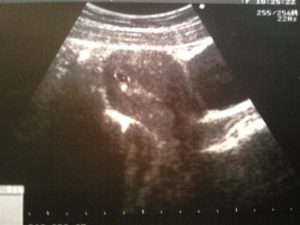

УЗИ – достоверный способ убедиться в том, что произошло прикрепление оплодотворенной яйцеклетки к стенке матки. В зависимости от срока, врач увидит только плодное яйцо или развивающегося в нем эмбриона.

На УЗИ зарождение новой жизни можно увидеть только при прикреплении зиготы к стенке матки, что происходит только на 7-10 день после зачатия. Часто врач на маленьком сроке видит в матке плодное яйцо, но не наблюдает в нем эмбриона.

Примерно с 4 акушерской недели врач может отметить наличие плодного яйца, изменившуюся структуру миометрия и другие косвенные признаки, указывающие на наступившую беременность.

Расшифровкой данных ультразвукового исследования должен заниматься только квалифицированный специалист. На первом УЗИ специалист определяет:

- Наличие каплевидного или округлого гипоэхогенного образования, диаметр которого составляет 0,3-0,5 см. От срока зависит и размер.

- Образование должно быть окружено тонкой оболочкой. Данное образование и есть плодное яйцо.

- Наличие желтого тела.

Во время первого ультразвука специалист-диагност выявляет образование с повышенной эхогенностью. Так выглядит плодное яйцо, величина которого позволяет судить о сроке данной беременности.

Ещё на мониторе будут видны желточный мешок, расположение зародыша, толщина внутреннего слоя матки. Врачи убедятся в отсутствии у женщины воспалений, полипов, кист и опухолей. Расшифровывать данные должен только профильный диагност.

Во время первого УЗИ обнаруживаются:

- круглое или каплевидное образование с низкой эхогенностью размером 3-5 мм. Его размер определяет срок;

- тонкая оболочка вокруг развивающегося ребёнка;

- жёлтое тело – оно вырабатывает прогестерон, способствующий сохранению плода.

На ранних сроках беременности можно различить такие признаки:

- можно увидеть круглое или овальное образование;

- диаметр образования будет составлять около 4-5 миллиметров;

- вокруг него можно увидеть тонкую оболочку;

- во время маточной беременности плод будет находиться в углу матки;